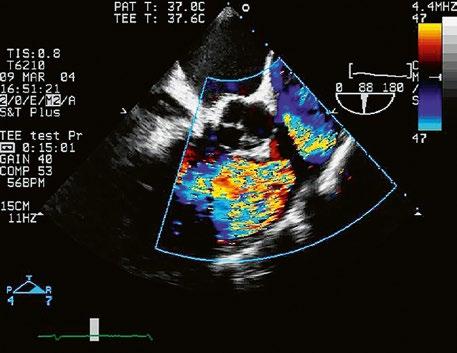

Obr. 45.1 Defekt septa síní typu II v TEE

AO – aorta, DDŽ – ústí dolní duté žíly do pravé síně, defekt septa síní je označen křížky, má předozadní průměr 22 mm, zasahuje blízko zadní stěny levé síně, LS – levá síň, PS – pravá síň

Obr. 45.2 Defekt septa síní typu II v TEE

AO – aorta, ASD – defekt septa síní typu secundum označen šipkou, zelenými křížky je označen malý přední rim k aortě, LS – levá síň, PS – pravá síň